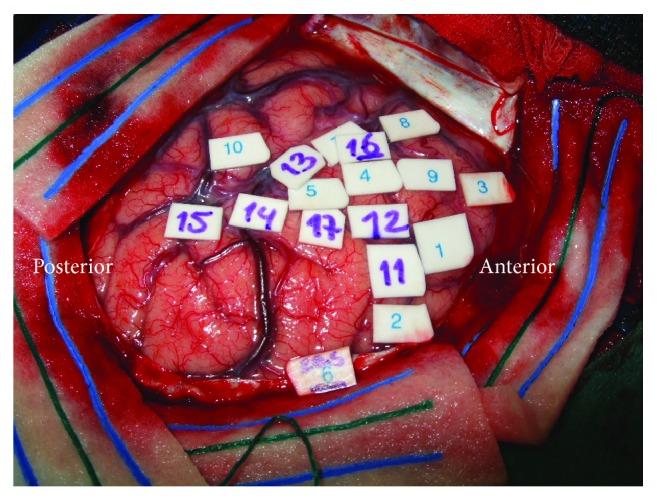

Awake surgery with electrocorticosubcortical stimulation is the golden standard treatment for gliomas in eloquent areas. Preoperatively, mostly mild cognitive disturbances are observed with postoperative deterioration. We describe pre- and postoperative profiles of 4 patients (P1-P4) with gliomas in "critical" language areas ("Broca," "Wernicke," and the arcuate fasciculus) undergoing awake surgery to get insight into the underlying mechanism of neuroplasticity. Neuropsychological examination was carried out preoperatively (at T1) and postoperatively (at T2, T3). At T1, cognition of P1 was intact and remained stable. P2 had impairments in all cognitive domains at T1 with further deterioration at T2 and T3. At T1, P3 had impairments in memory and executive functions followed by stable recovery. P4 was intact at T1, followed by a decline in a language test at T2 and recovery at T3. Intraoperatively, in all patients language positive sites were identified. Patients with gliomas in "critical" language areas do not necessarily present cognitive disturbances. Surgery can either improve or deteriorate (existing) cognitive impairments. Several factors may underlie the plastic potential of the brain, for example, corticosubcortical networks and tumor histopathology. Our findings illustrate the complexity of the underlying mechanism of neural plasticity and provide further support for a "hodotopical" viewpoint.

采用皮质-皮质下电刺激的清醒手术是治疗功能区胶质瘤的金标准。术前,大多观察到轻度认知障碍,术后会恶化。我们描述了4例(P1 - P4)胶质瘤位于“关键”语言区(“布洛卡区”、“韦尼克区”和弓状束)的患者在接受清醒手术前后的情况,以深入了解神经可塑性的潜在机制。术前(T1)和术后(T2、T3)均进行了神经心理学检查。在T1时,P1的认知功能完好且保持稳定。P2在T1时所有认知领域均有损害,在T2和T3时进一步恶化。在T1时,P3存在记忆和执行功能损害,随后稳定恢复。P4在T1时完好,随后在T2时语言测试成绩下降,在T3时恢复。术中,所有患者均确定了语言阳性部位。胶质瘤位于“关键”语言区的患者不一定存在认知障碍。手术可能改善或恶化(已有的)认知损害。大脑的可塑性潜力可能有几个因素,例如,皮质-皮质下网络和肿瘤组织病理学。我们的研究结果说明了神经可塑性潜在机制的复杂性,并为“路径特异性”观点提供了进一步支持。